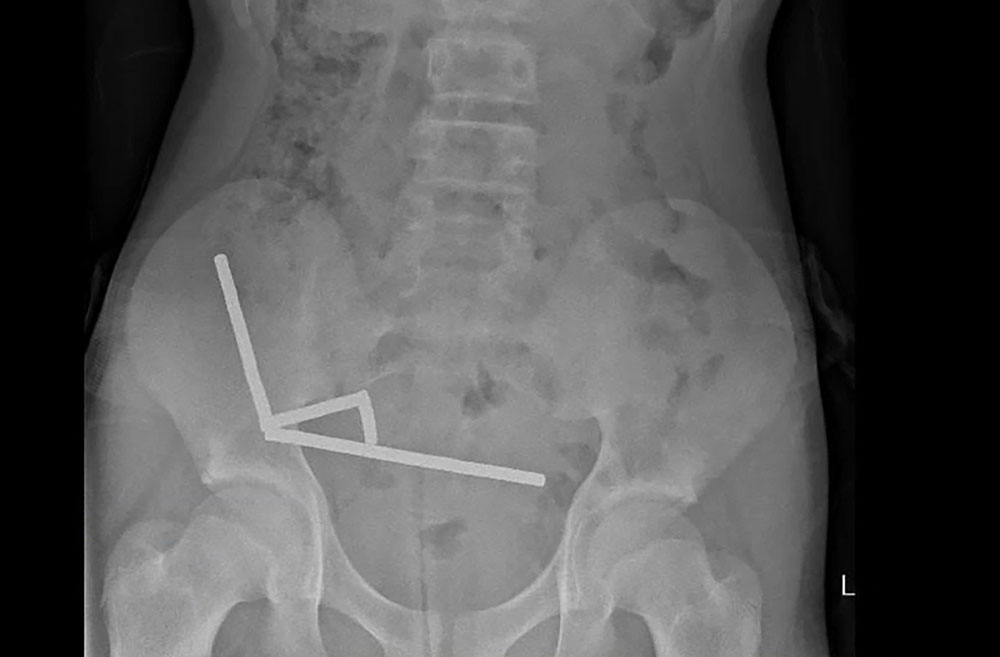

An X-ray showed the magnets had clumped together in four straight lines inside the child's intestines.

"These appeared to be in separate parts of bowel adhered together due to magnetic forces," they said.